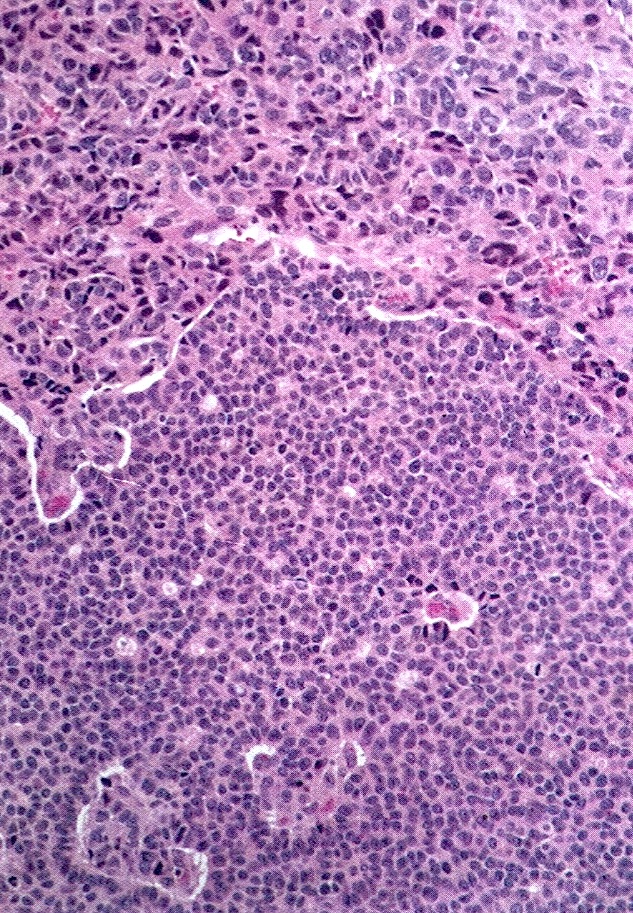

- Small, bland, cuboidal to polygonal cells with scant cytoplasm and pale, uniform angulated and usually grooved nuclei (coffee bean)

- Various patterns, including diffuse (the most common), trabecular and corded, insular, microfollicular (resembling Call-Exner bodies of the Graafian follicles: small follicle-like structures filled with eosinophilic material) and macrofollicular (the least common)

- Usually a mixed growth pattern is seen

- Mitotic activity is usually not brisk (< 3/10 high power fields)

- Stroma is usually hypervascular with variable amounts of fibroblasts and theca cells

Microscopic (histologic) images

Contributed by Shabnam Zarei, M.D. and Sharon Bihlmeyer, M.D.

AFIP images